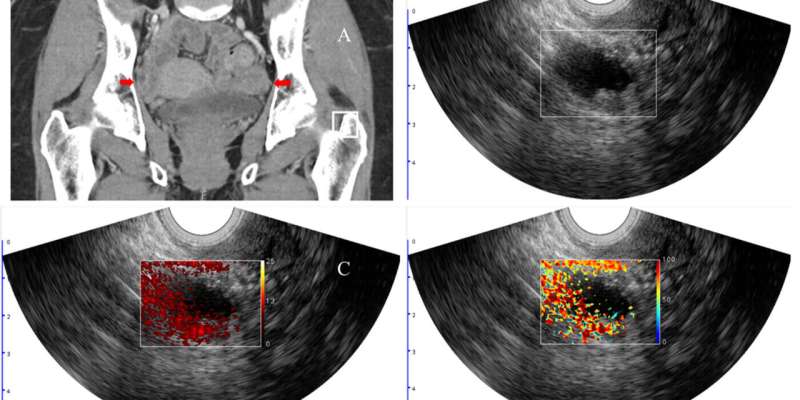

Researchers and clinicians at Washington University in St. Louis have found a way to improve the standard of care diagnostic accuracy of potentially cancerous lesions in the ovaries and adnexal regions, or the fallopian tubes, by incorporating functional biomarkers with photoacoustic imaging, a technique that illuminates tissue with near-infrared light at specific wavelengths that are absorbed differently by oxygenated and deoxygenated hemoglobin.

“Photoacoustic imaging combined with ultrasound provides complementary diagnostic imaging data involving structure and function,” Zhu said. “The ultrasound localizes the lesion, and the photoacoustic images inform tumor hemoglobin content and percent of blood oxygen saturation.”

Hemoglobin concentration and blood oxygen saturation provide functional information on the vasculature within the tissue as well as oxygen consumption. Malignant lesions generally have higher hemoglobin concentration due to tumor angiogenesis and lower blood oxygen saturation due to high tumor metabolism, a finding that helps differentiate benign from malignant lesions.

In a clinical study conducted by the team, 68 patients scheduled to have their ovaries surgically removed underwent clinical ultrasound as well as the combined photoacoustic and ultrasound technology (PAT/US) that Zhu’s team developed. Among the patients, 14 had malignant lesions in their ovaries or adnexal regions, two patients had malignant fallopian tubes and 52 patients had benign lesions.

Each lesion was graded by two radiologists using the Ovarian-Adnexal Reporting and Data System (O-RADS), which classifies risk for malignancy in six categories, from O-RADS 0 being an incomplete evaluation, to O-RADS 5, meaning a more than 50% risk of malignancy.

When comparing the malignant and benign lesions, the relative total hemoglobin in the patients with malignant lesions in the ovaries and in the adnexal region was 1.8 times higher than in those with benign lesions. The blood oxygen saturation was 5% lower in those with malignant lesions, though it was not a statistically significant difference. Presence of the cancer antigen CA 125 was significantly different in patients with malignant lesions compared with patients with three common types of benign lesions but not significantly different from the group with endometriosis, abscess, adhesions, infarction or torsion.

Ultimately, the team found that the most important predictors of malignancy were relative total hemoglobin, the O-RADS score, presence of the cancer antigen CA 125 and percentage of blood oxygen saturation (sO2). Their model that incorporated all four features had an area under the receiving characteristic curve (AUC) of 0.97, a metric used in medical imaging diagnosis to measure a model’s performance. A score of 1 indicates ideal model performance.